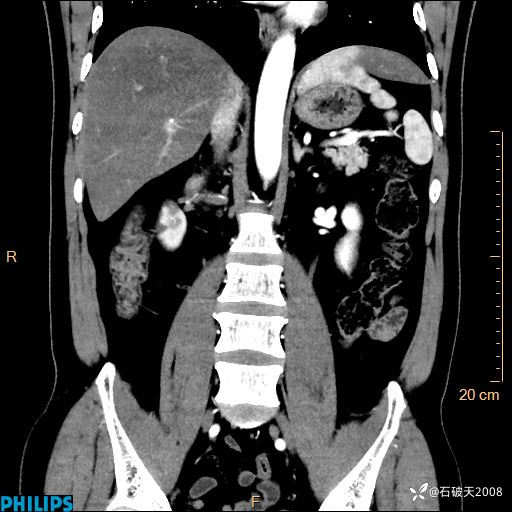

平扫轴位

增强轴位

冠状位